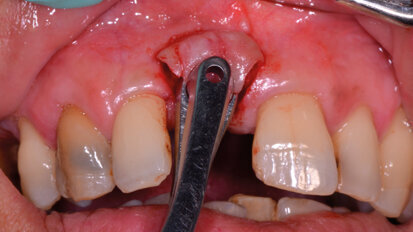

L’adherence al trattamento chirurgico, dopo l’igiene orale professionale. Case report

Nella pratica clinica l’esigenza estetica del paziente è comunque il primum movens dei trattamenti odontoiatrici. Il ruolo ...